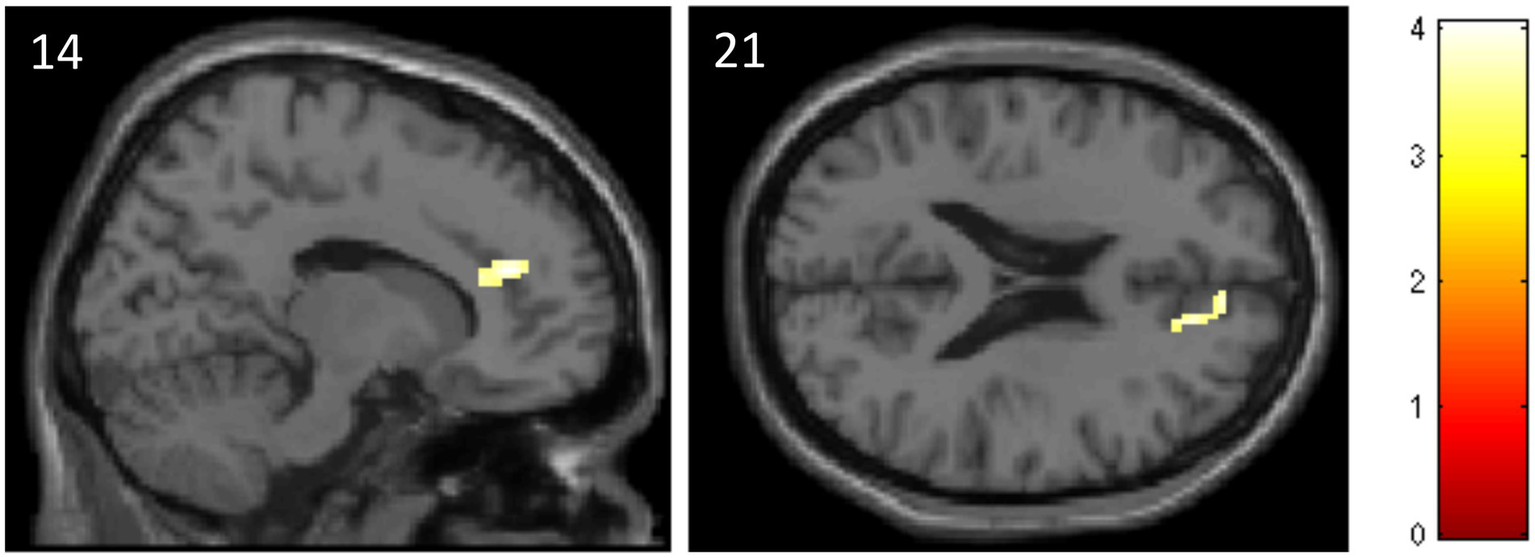

The ROI analysis revealed that subjects of the ATT group, compared to the sham ATT group, showed decreased activation in the ACC at T1 when presented with incongruent stimuli (MNI: x = 14; y = 40; z = 21; p = 0.045; Table 2, see Figure 5). Other ATT-dependent results regarding congruent or neutral stimuli were not observed. Triple difference analyzes {ATT [T1(incongruent > neutral) > T0(incongruent > neutral)] > sham ATT [T1(incongruent > neutral) > T0(incongruent > neutral)]} did not show any significant effects independent of the direction of testing [e.g., also for (incongruent < neutral) and (T1 < T0)].

Table 2

| location (AAL) | Hemisphere | x | y | z | Cluster size | p-value | T-value (peak voxel) |

|---|---|---|---|---|---|---|---|

| Anterior cingulate cortex | R | 14 | 40 | 20 | 72 (576 mm3) | <0.001 | 4.04 |

Data and coordinates of the activation changes shown in Figure 5.

Figure 5

Decreased activation in the anterior cingulate cortex in the ATT group compared to the sham ATT group during incongruent trials of the emotional dot probe task at T1.

The fMRI results of the emotional dot probe task showed significantly lower activation in the ACC during incongruent trials at T1 when comparing the ATT to the sham ATT group. Since incongruent trials theoretically require enhanced attentional disengagement from the negatively connoted word, these findings may indicate that the ACC may play a key role in the neuronal mechanisms of attentional disengagement. Furthermore, these results suggest that ATT potentially impacts ACC activity, which in this case might represent the neuronal equivalent of faster attention allocation. In addition, this hints at the CCN as the attentional network, which is influenced by ATT, as the ACC is an integral part of the CCN.